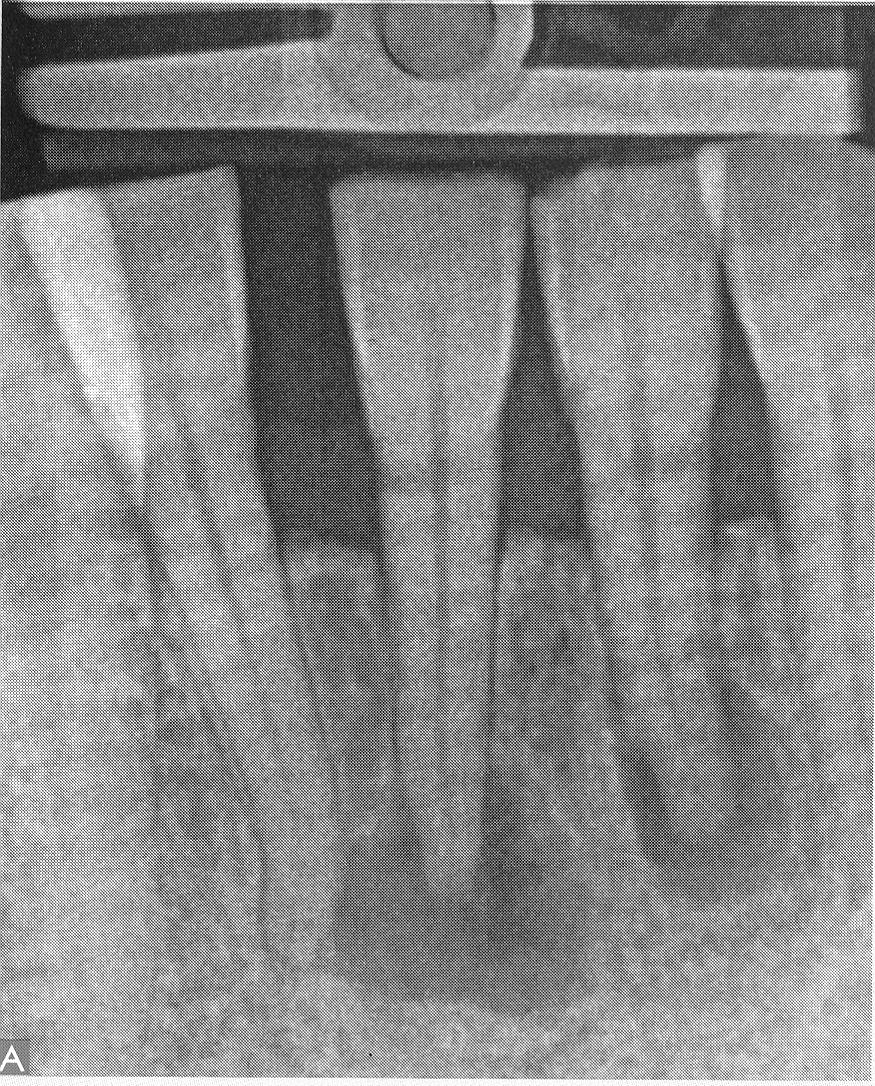

Pacjent zgłosił się z do gabinetu stomatologicznego z powodu znacznego przebarwienia koron zębów 31 i 41. W wywiadzie nie podawał żadnych objawów bólowych, a jedynie dawny uraz zębów w odcinku przednim żuchwy. Podczas badania stomatologicznego wewnątrzustnego stwierdzono brak reakcji na bodźce termiczne i na test nawiercania oraz dodatni objaw Smrekera. Wykonano zdjęcie Rtg (przedstawione poniżej). Przeprowadzono antyseptyczne leczenie kanałowe zębów 31 i 41. Na podstawie objawów klinicznych oraz obrazu RTG wskaż prawidłową diagnozę: